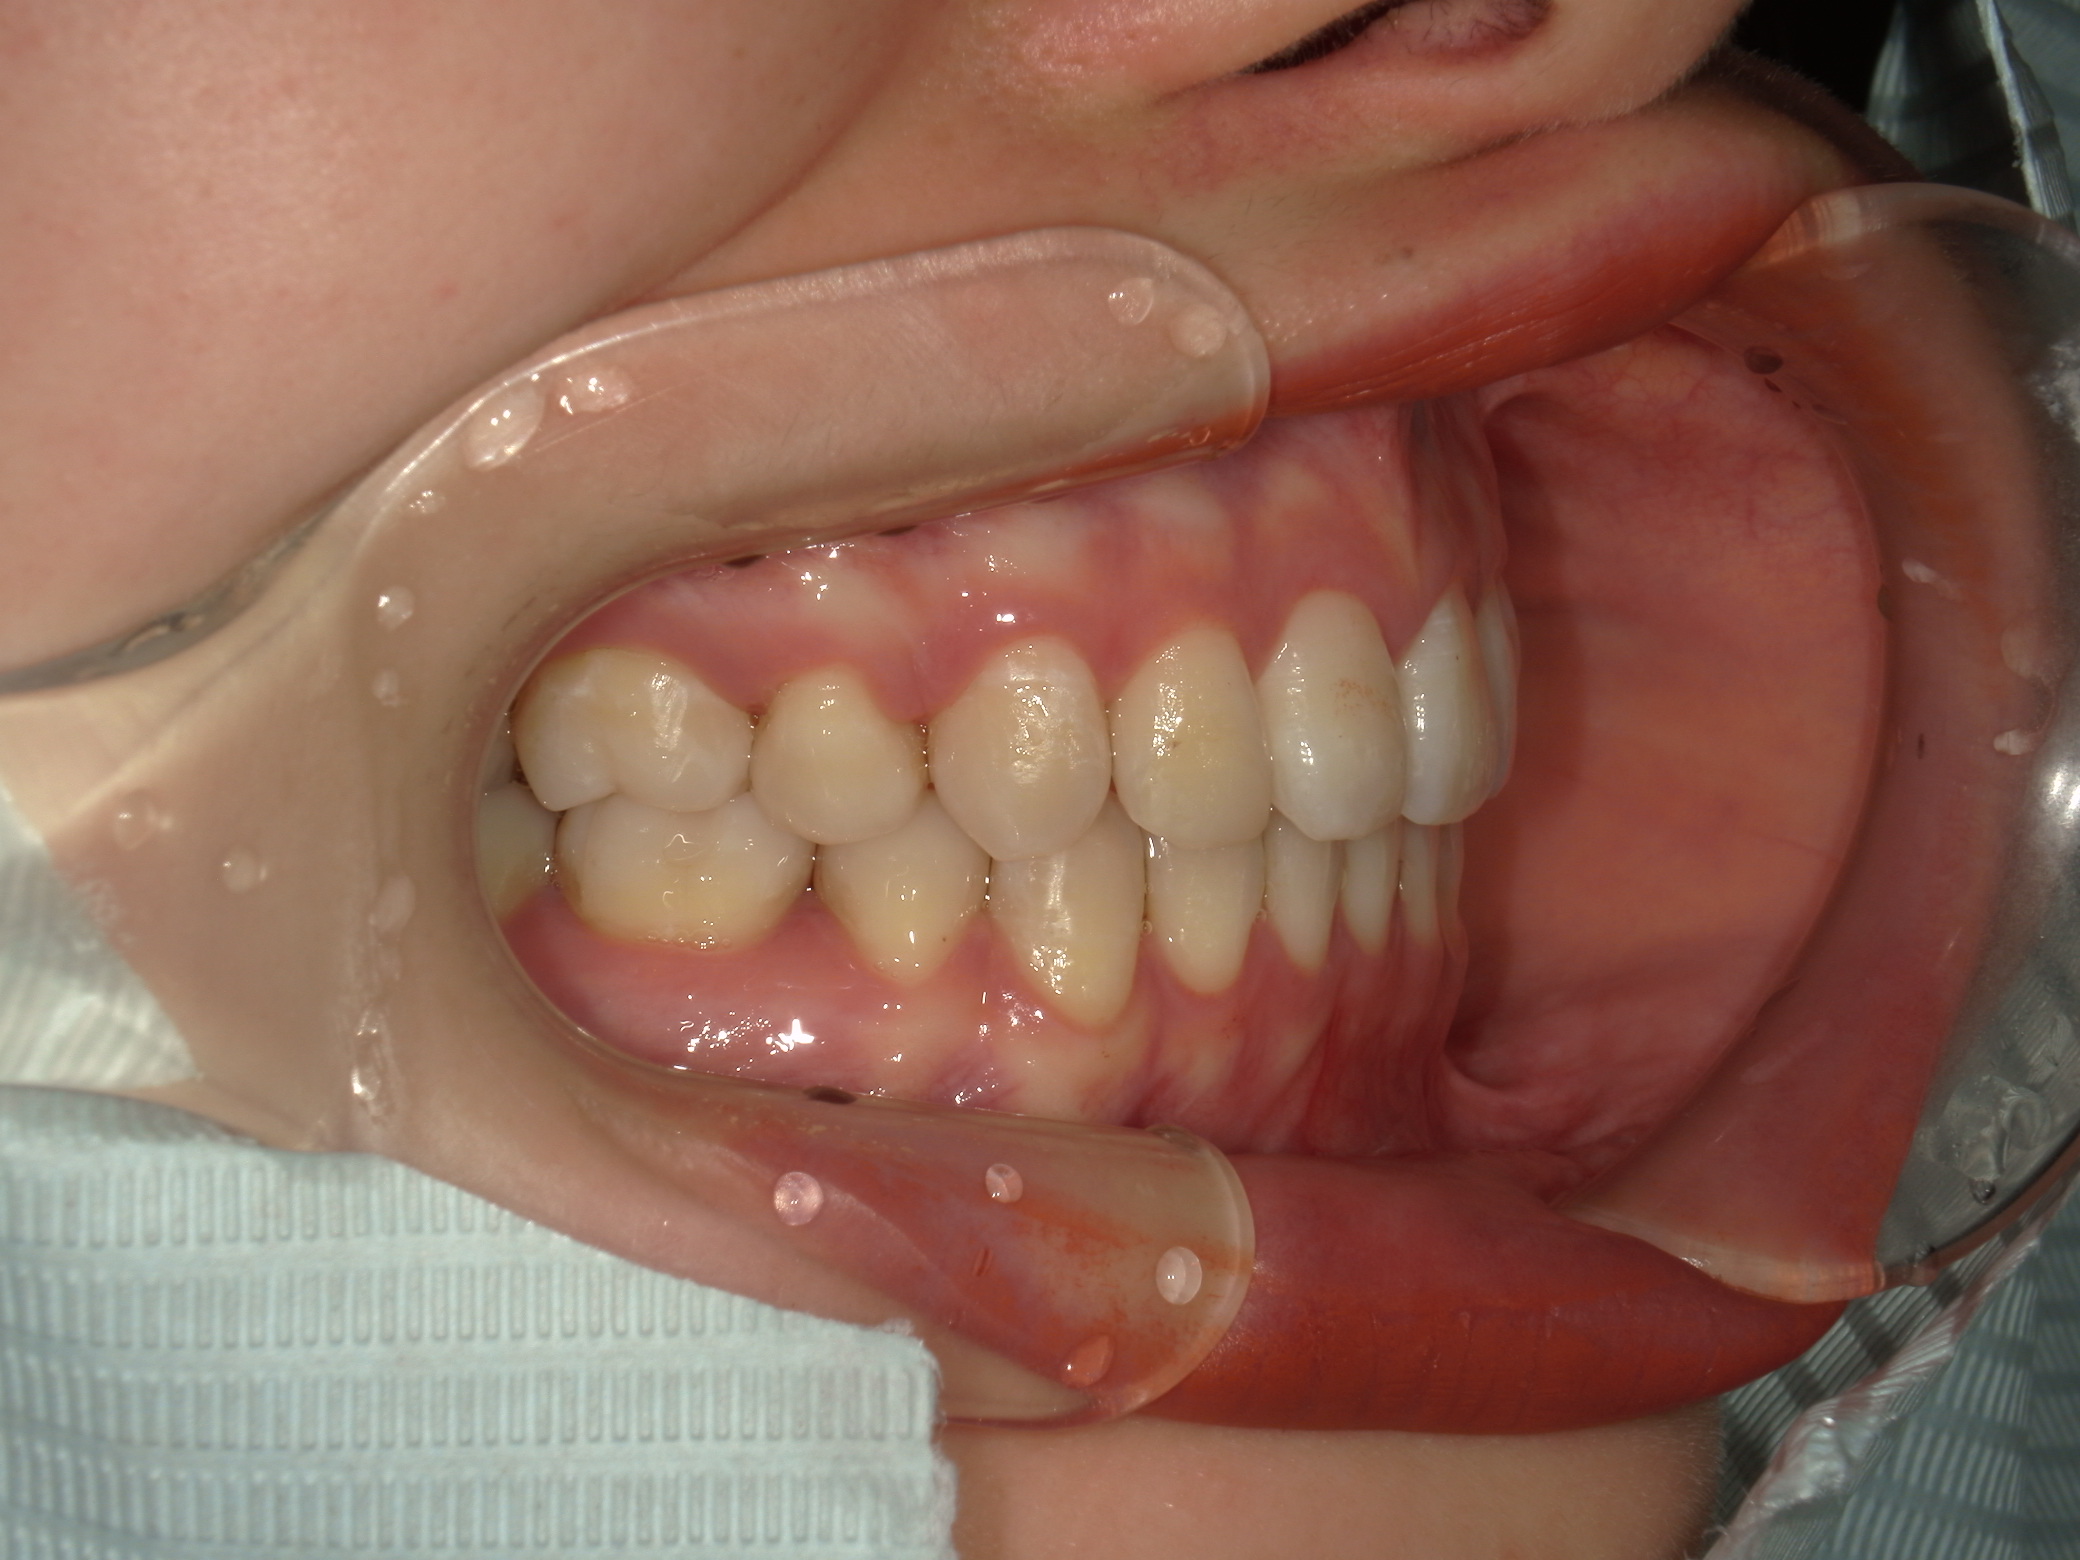

ご相談内容・お悩み

口元の突出感

口元の突出を主訴に来院。

上下小臼歯抜歯により突出感を改善する計画を立てた。確立した咬合を崩さないように治療を進める事を目標とした。

患者はハーフリンガル矯正を希望した。

治療後、口元の突出感の改善、咬合関係は維持することができた。